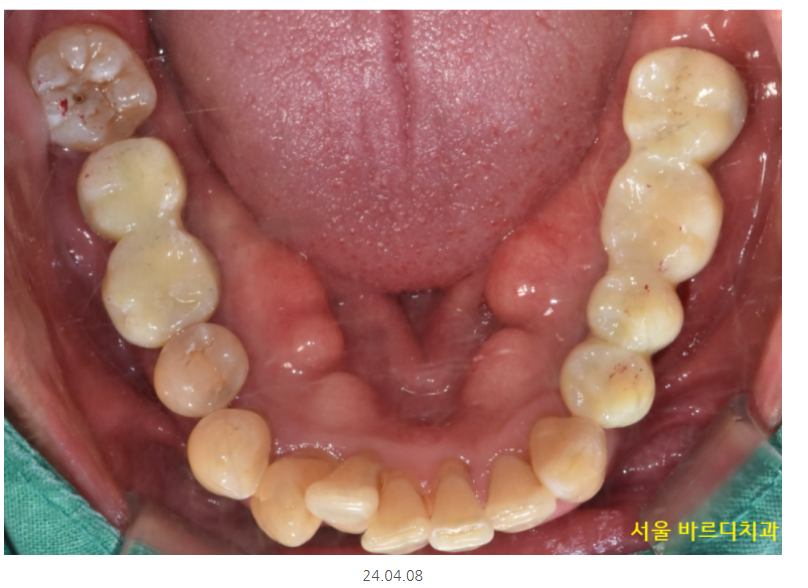

오늘 소개해드릴 환자분

하루 2갑씩 피는 환자분이셨습니다.

환자분을 처음 뵈었을 때

솔직히 말씀드려 안 흔들리는 치아가 없었습니다.

잇몸이 많이 망가졌어요.

아랫니는 2개 없음

이건 이미 뽑힌 상태만 세었을 때이고

뽑을 치아도 상당했습니다.

환자분처럼 양쪽 어금니가 다 없고

임플란트 뼈이식을 많이 해야할경우

그동안 치아 상태는 이런 모습이셨어요.

어금니는 없고

식사는 하셔야하니까

7개월동안 임시틀니로 식사 하실 수 있게 했습니다.

길동 치과 완성 후 사진입니다.